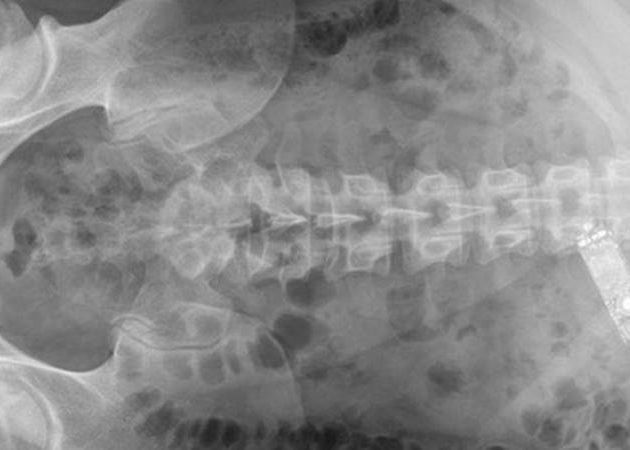

Detinutul unei inchisori din Irlanda a inghitit un telefon ca sa-l ascunda insa device-ul a ramas blocat in stomac. Barbatul de 29 de ani a vomitat timp de 4 ore inainte sa fie dus la spital de urgenta.

Medicii l-au sedat inainte sa introduca un tub cu un mic cleste si o camera - pana la urma a fost necesara operarea detinutului pentru ca telefonul era blocat in stomac.

Cazul a fost raportat in International Journal of Surgery Case Reports - doctorii si-au sfatuit colegii pe viitor sa primeasca acordul de la pacient pentru o eventuala operatie inainte sa-l sedeze.